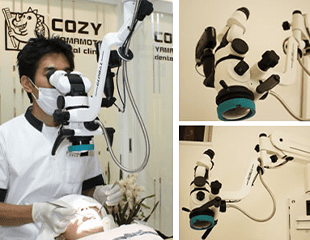

治療に必要な三種の神器

マイクロスコープ・CT・CAD-CAMシステム

マイクロスコープ

当医院では、2008年から3台のマイクロスコープを保険・自由診療かかわらず使用しています。

また、クリーニング業務にも使用することによって、より深くまで汚れを除去することが可能となります。約15倍の拡大下で処理することにより、肉眼で捉えにくい部分を正確に確認、把握できるため精度の高い歯科治療を患者様にご提供できます。